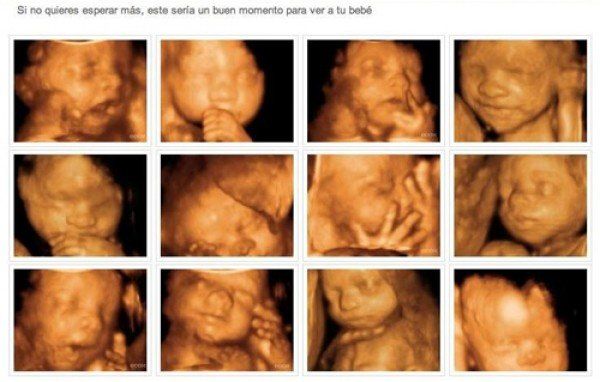

Conozca el excelente trabajo que desarrollamos en relación a la medicina fetal. Realizamos ecografía temprana del embarazo, crecimiento del embrión, entre otros servicios.